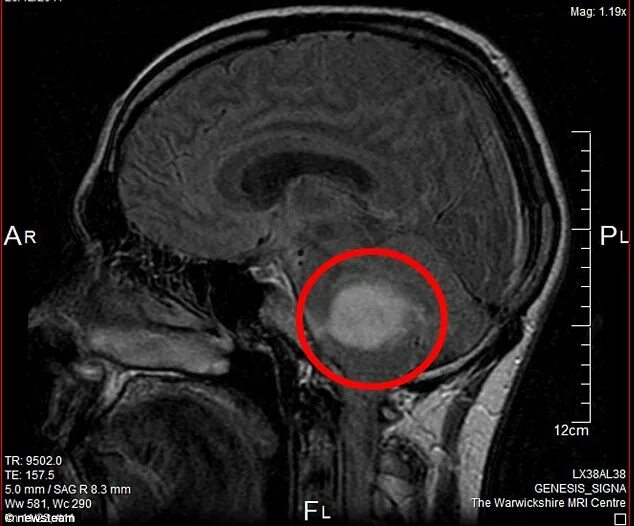

Как выглядит опухоль на снимках